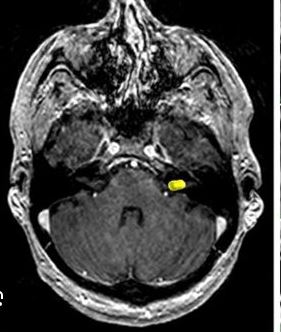

Μηνιγγίωμα: Τύποι, Συμπτώματα, Διάγνωση, Θεραπεία, Κίνδυνος Κακοήθειας και Νέες Εξελίξεις 2026